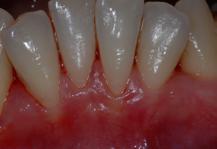

Figure 8.6.a : La gencive est très fine, on voit les racines par transparence. Les mouvements orthodontiques pour aligner les dents risqueraient d’aggraver la situation.

Figure 8.6.b : Grâce à la greffe, la gencive est suffisamment épaisse pour supporter le traitement orthodontique.